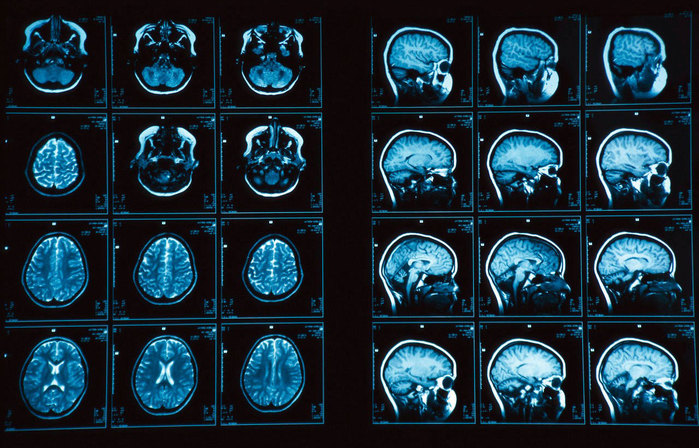

Медицина в наше время при выявлении проблем с сосудами и исследовании различных онкозаболеваний прибегает к методу томографии с контрастом. Данное исследование проводится, как на компьютерном, так и на магнитно-резонансном томографе. Принцип работы предельно прост. Пациенту внутривенно или перорально, то есть внутрь через рот, вводится индикаторное вещество. Оно скапливается в проблемной зоне, будь это злокачественная опухоль или закупоренный сосуд. Проведение процедуры томографии даст более четкие границы проблемной области и наиболее точную информацию о недуге в целом. КТ, по методу контрастирования, Томография с контрастом, как проводят, чем отличается от бесконтрастной диагностикииспользует жирорастворимые и водорастворимые индикаторы, содержащие в своем составе йод. Следует помнить, что некоторые пациенты имеют на него аллергию. В клинике обязаны проверить больного на наличие аллергических реакций. Для МРТ с целью повышения качества изображения внутривенно водится красильное вещество, содержащее в себе гадолиний или его соли, уровень визуализации при этом значительно возрастает.

Томография, применяющая контрастирование, обрела широкое распространение при изучении различных групп органов. Начиная от сердечно сосудистой системы, дыхательной, пищеварительной и заканчивая органами мочевыделительной системы. Такой способ позволяет выявлять онкологию печени, образования кист, язв желудка двенадцатиперстной кишки и многое другое. При всех преимуществах данного метода обязательно нужно учитывать один важный факт. КТ работает с гамма излучением и противопоказан к частому применению. Соли гадолиния являются токсичными в связи, с чем многократное магнитно-резонансное исследование так же не приемлемо. Выбор метода томографического обследования с контрастированием или без него определяет ваш лечащий врач.